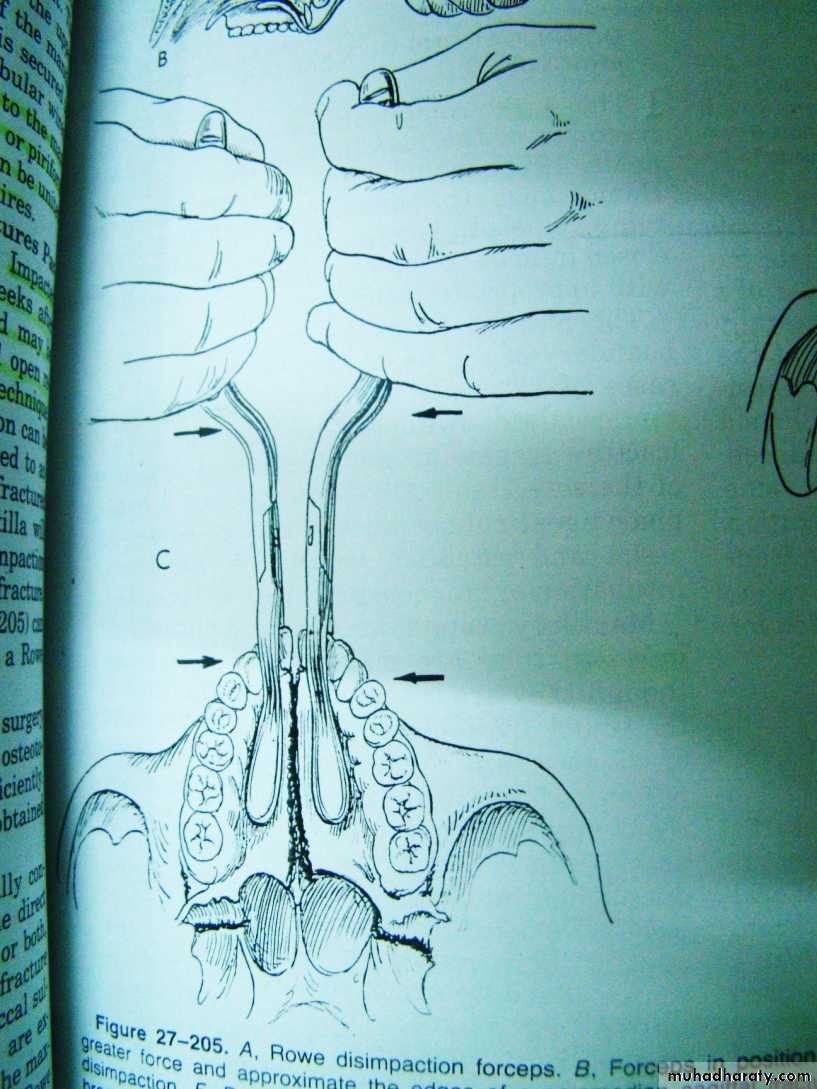

Treatment : reduction

Reduction of maxillary fractures: (1) Rowe’s maxillary disimpaction forceps, (2) Hayton William’s disimpaction forcep

Reduction of maxilla using rowe disimpaction forceps and walsham’s disimpaction forceps